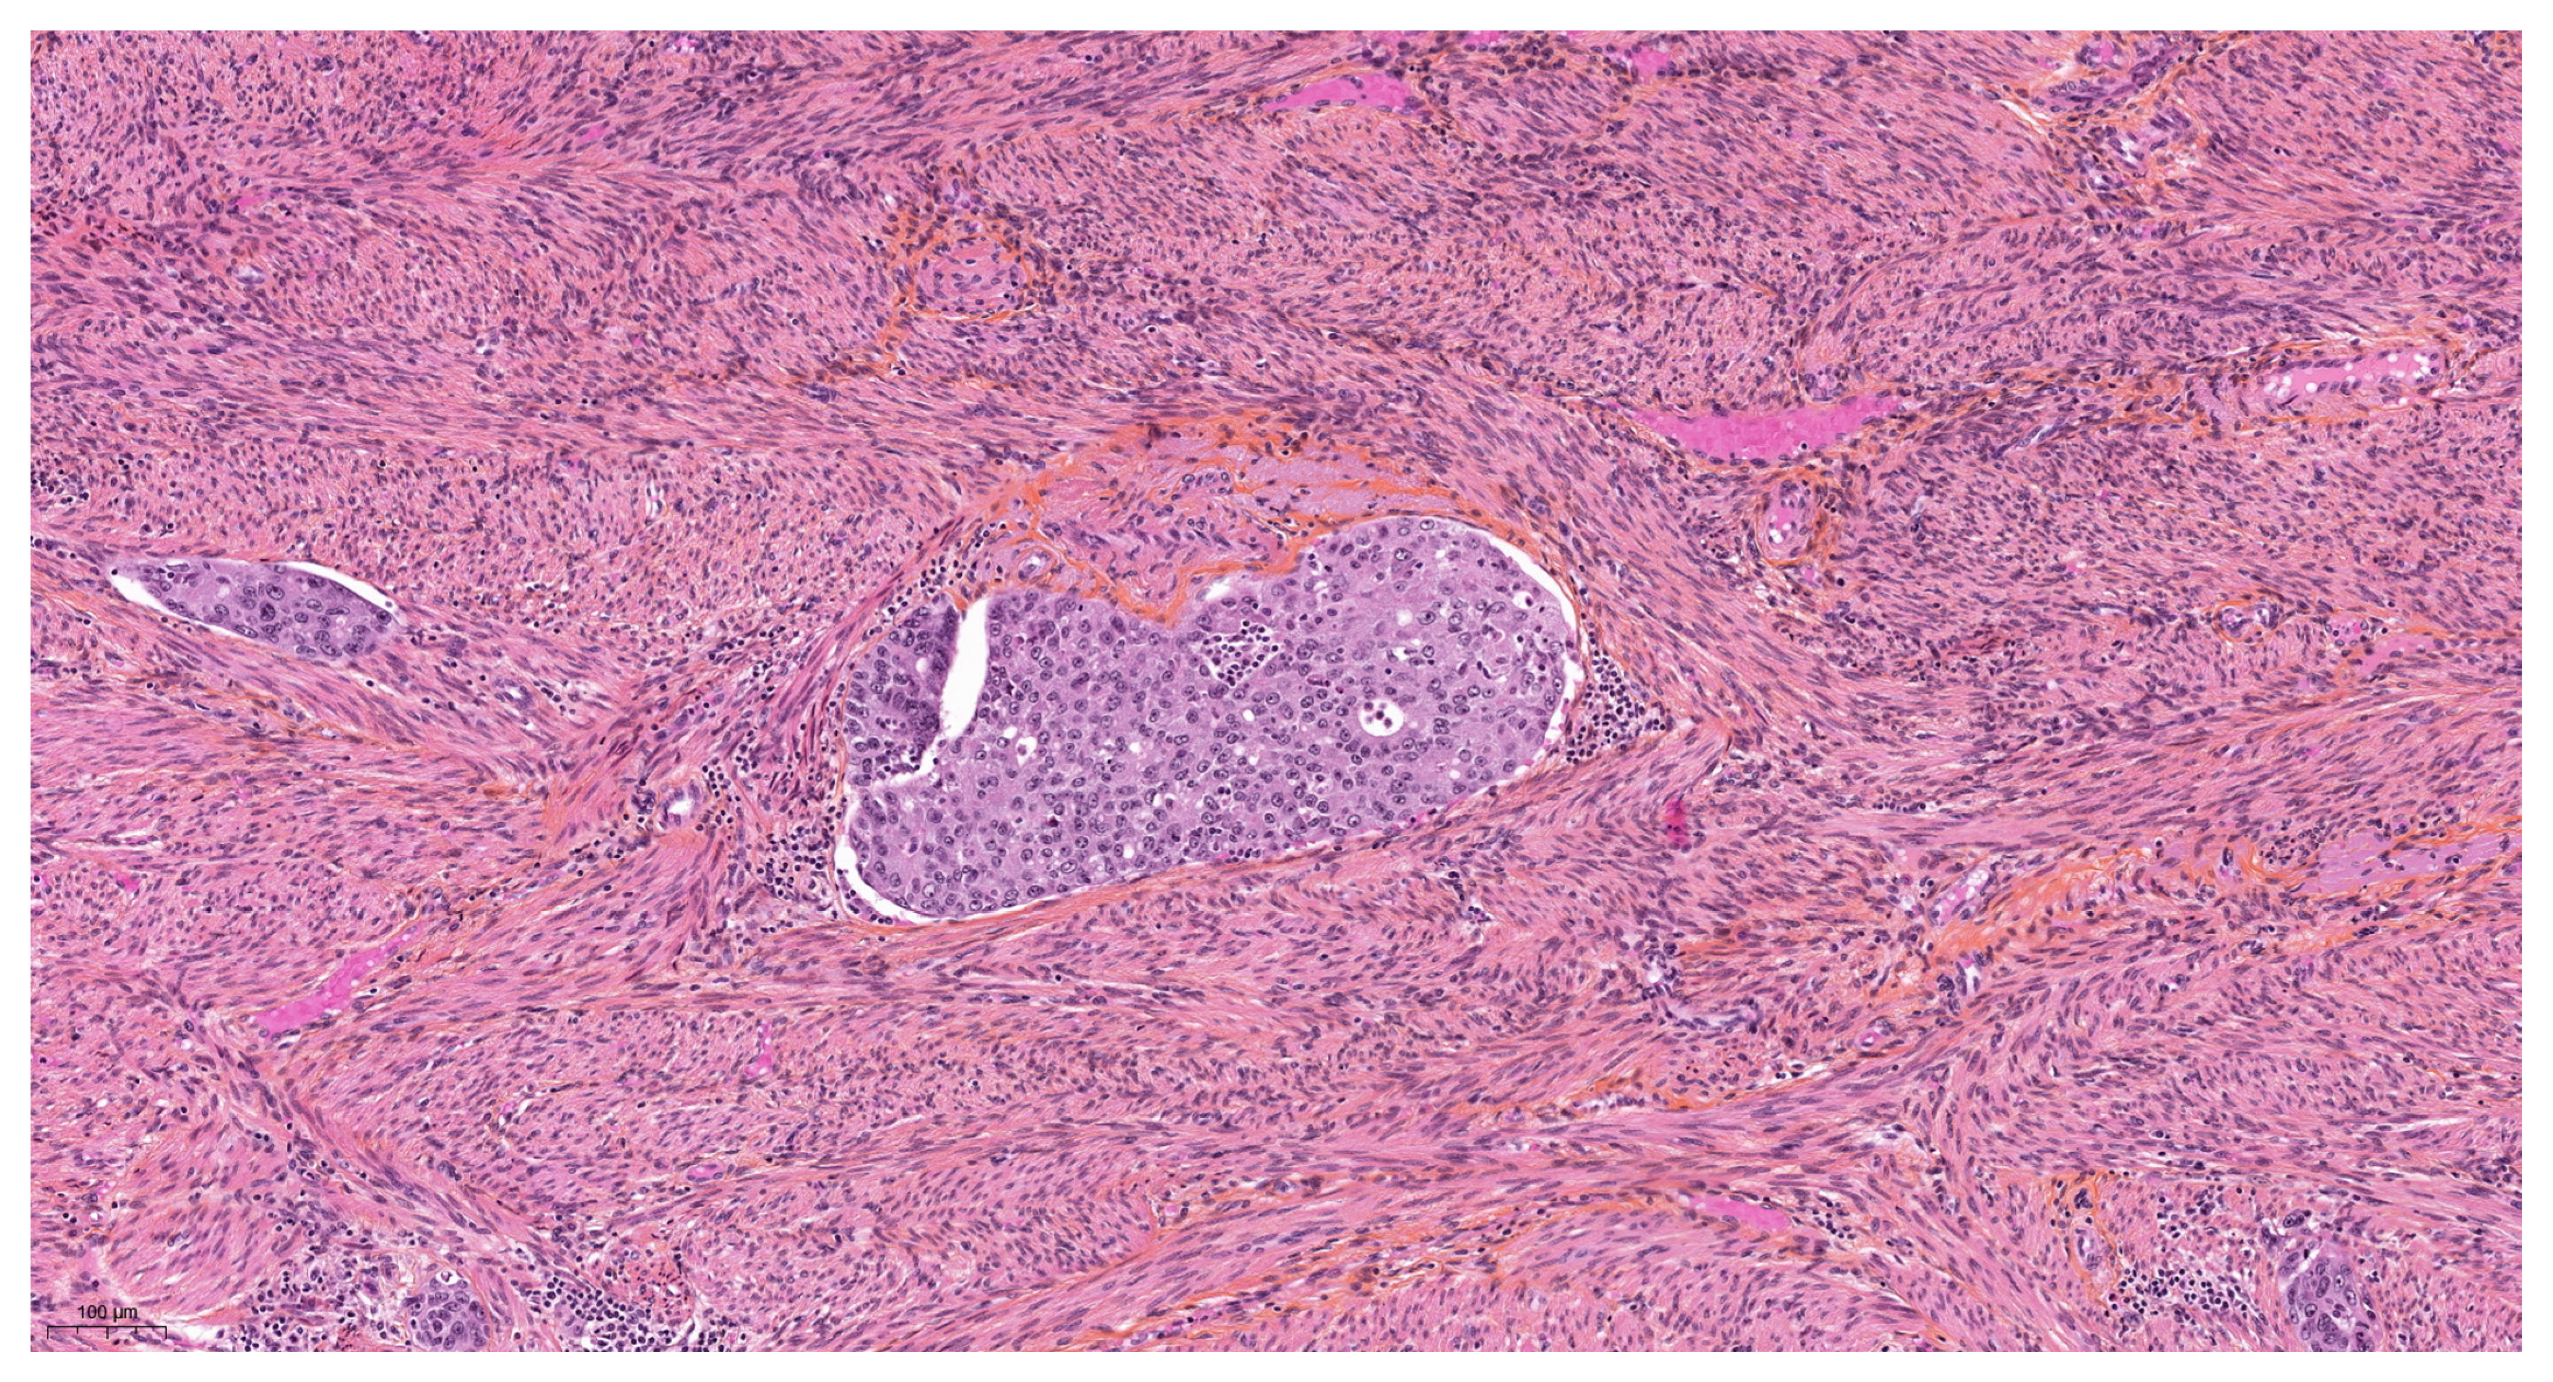

| Vascular pseudoinvasion | |

| Present | 14 (23.7) |

| Absent | 46 (76.6) |